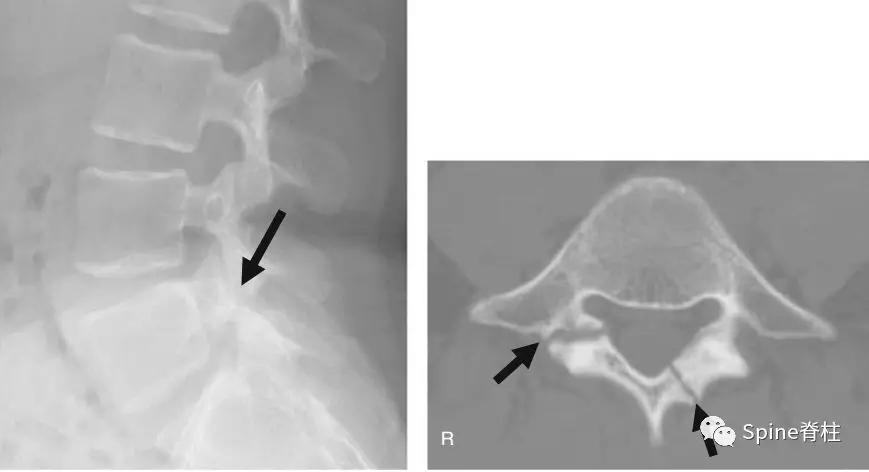

图:箭头所指为离断的椎体后缘

CT是诊断最有效的检查手段

图:箭头所指为苏格兰狗脖子断了

图:腰椎斜位片,图中黑色箭头所示为峡部裂

图:CT所示峡部裂(长箭头),可别认为是棘突骨折